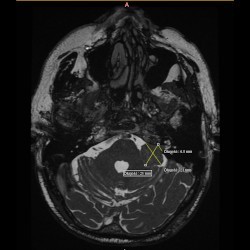

Guz lewego kąta mostowo-móżdżkowego

W dn. 15.09.2021 do Poradni Radioterapii zgłosił się chory z niedosłuchem lewostronnym i zaburzeniami równowagi. W wyniku MRI głowy w lewym kącie mostowo-móżdżkowym widoczna była lita masa silnie wzmacniającego się guza, który cienką wypustką wpuklał się do światła przewodu słuchowego wew.